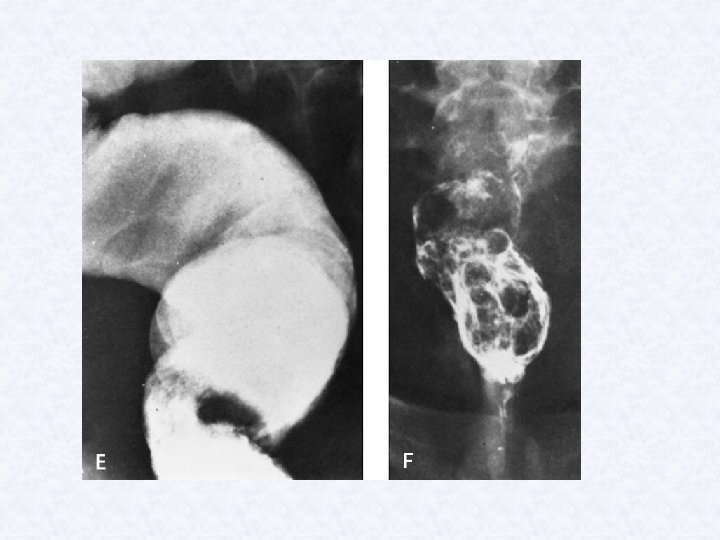

2 -Egg deposition and extrusion Ø Most eggs traped in sucbmucosa and muscularis of bladder. Initially painless terminal haematuria for months to years, then burning micturition. Cystoscopy shows hyperplasia and inflammation of lower bladder, initial papillomata.

3 - Tissue proliferation& repair: - Generalized hyperplasia and fibrosis of bladder, lower ureter, sandy patches, squamous cell carcinoma. b- Calaculi: obstructive uropathy leading to: -retrograde infection. -hydronephrosis and renal failure.

Ancillary investigation in schistosomiasis: • Endoscopy: papillomta • Radiological • - Ultrasound for liver periportal fibrosis. - X-ray calcification , obstructive uropathy Pulmonary changes e. g. cor pulmonale Serological tests: ELISA mainly survey method to detect: Ab : light or old infection Ag : in active infection.